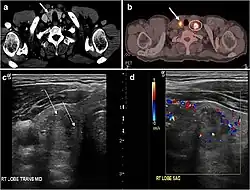

Fig. 4. A 45-year-old male patient presented with anterior mediastinal metastatic PTC lesions and occult primary on imaging. Histopathology examination of the resected thyroid gland revealed micro-foci of PTC; the largest, in the isthmus, measured 4 mm. a transverse greyscale ultrasound of the thyroid demonstrates homogeneous gland with normal echogenicity and size. No focal lesion or micro-calcifications. b Non-enhanced CT scan obtained as part of PET/CT examination shows a heterogeneous, large, relatively dense anterior mediastinal mass (white arrow) with peripheral calcification (arrowheads). Thyroid gland has normal CT appearance with no abnormal FDG uptake (not shown).[1] -